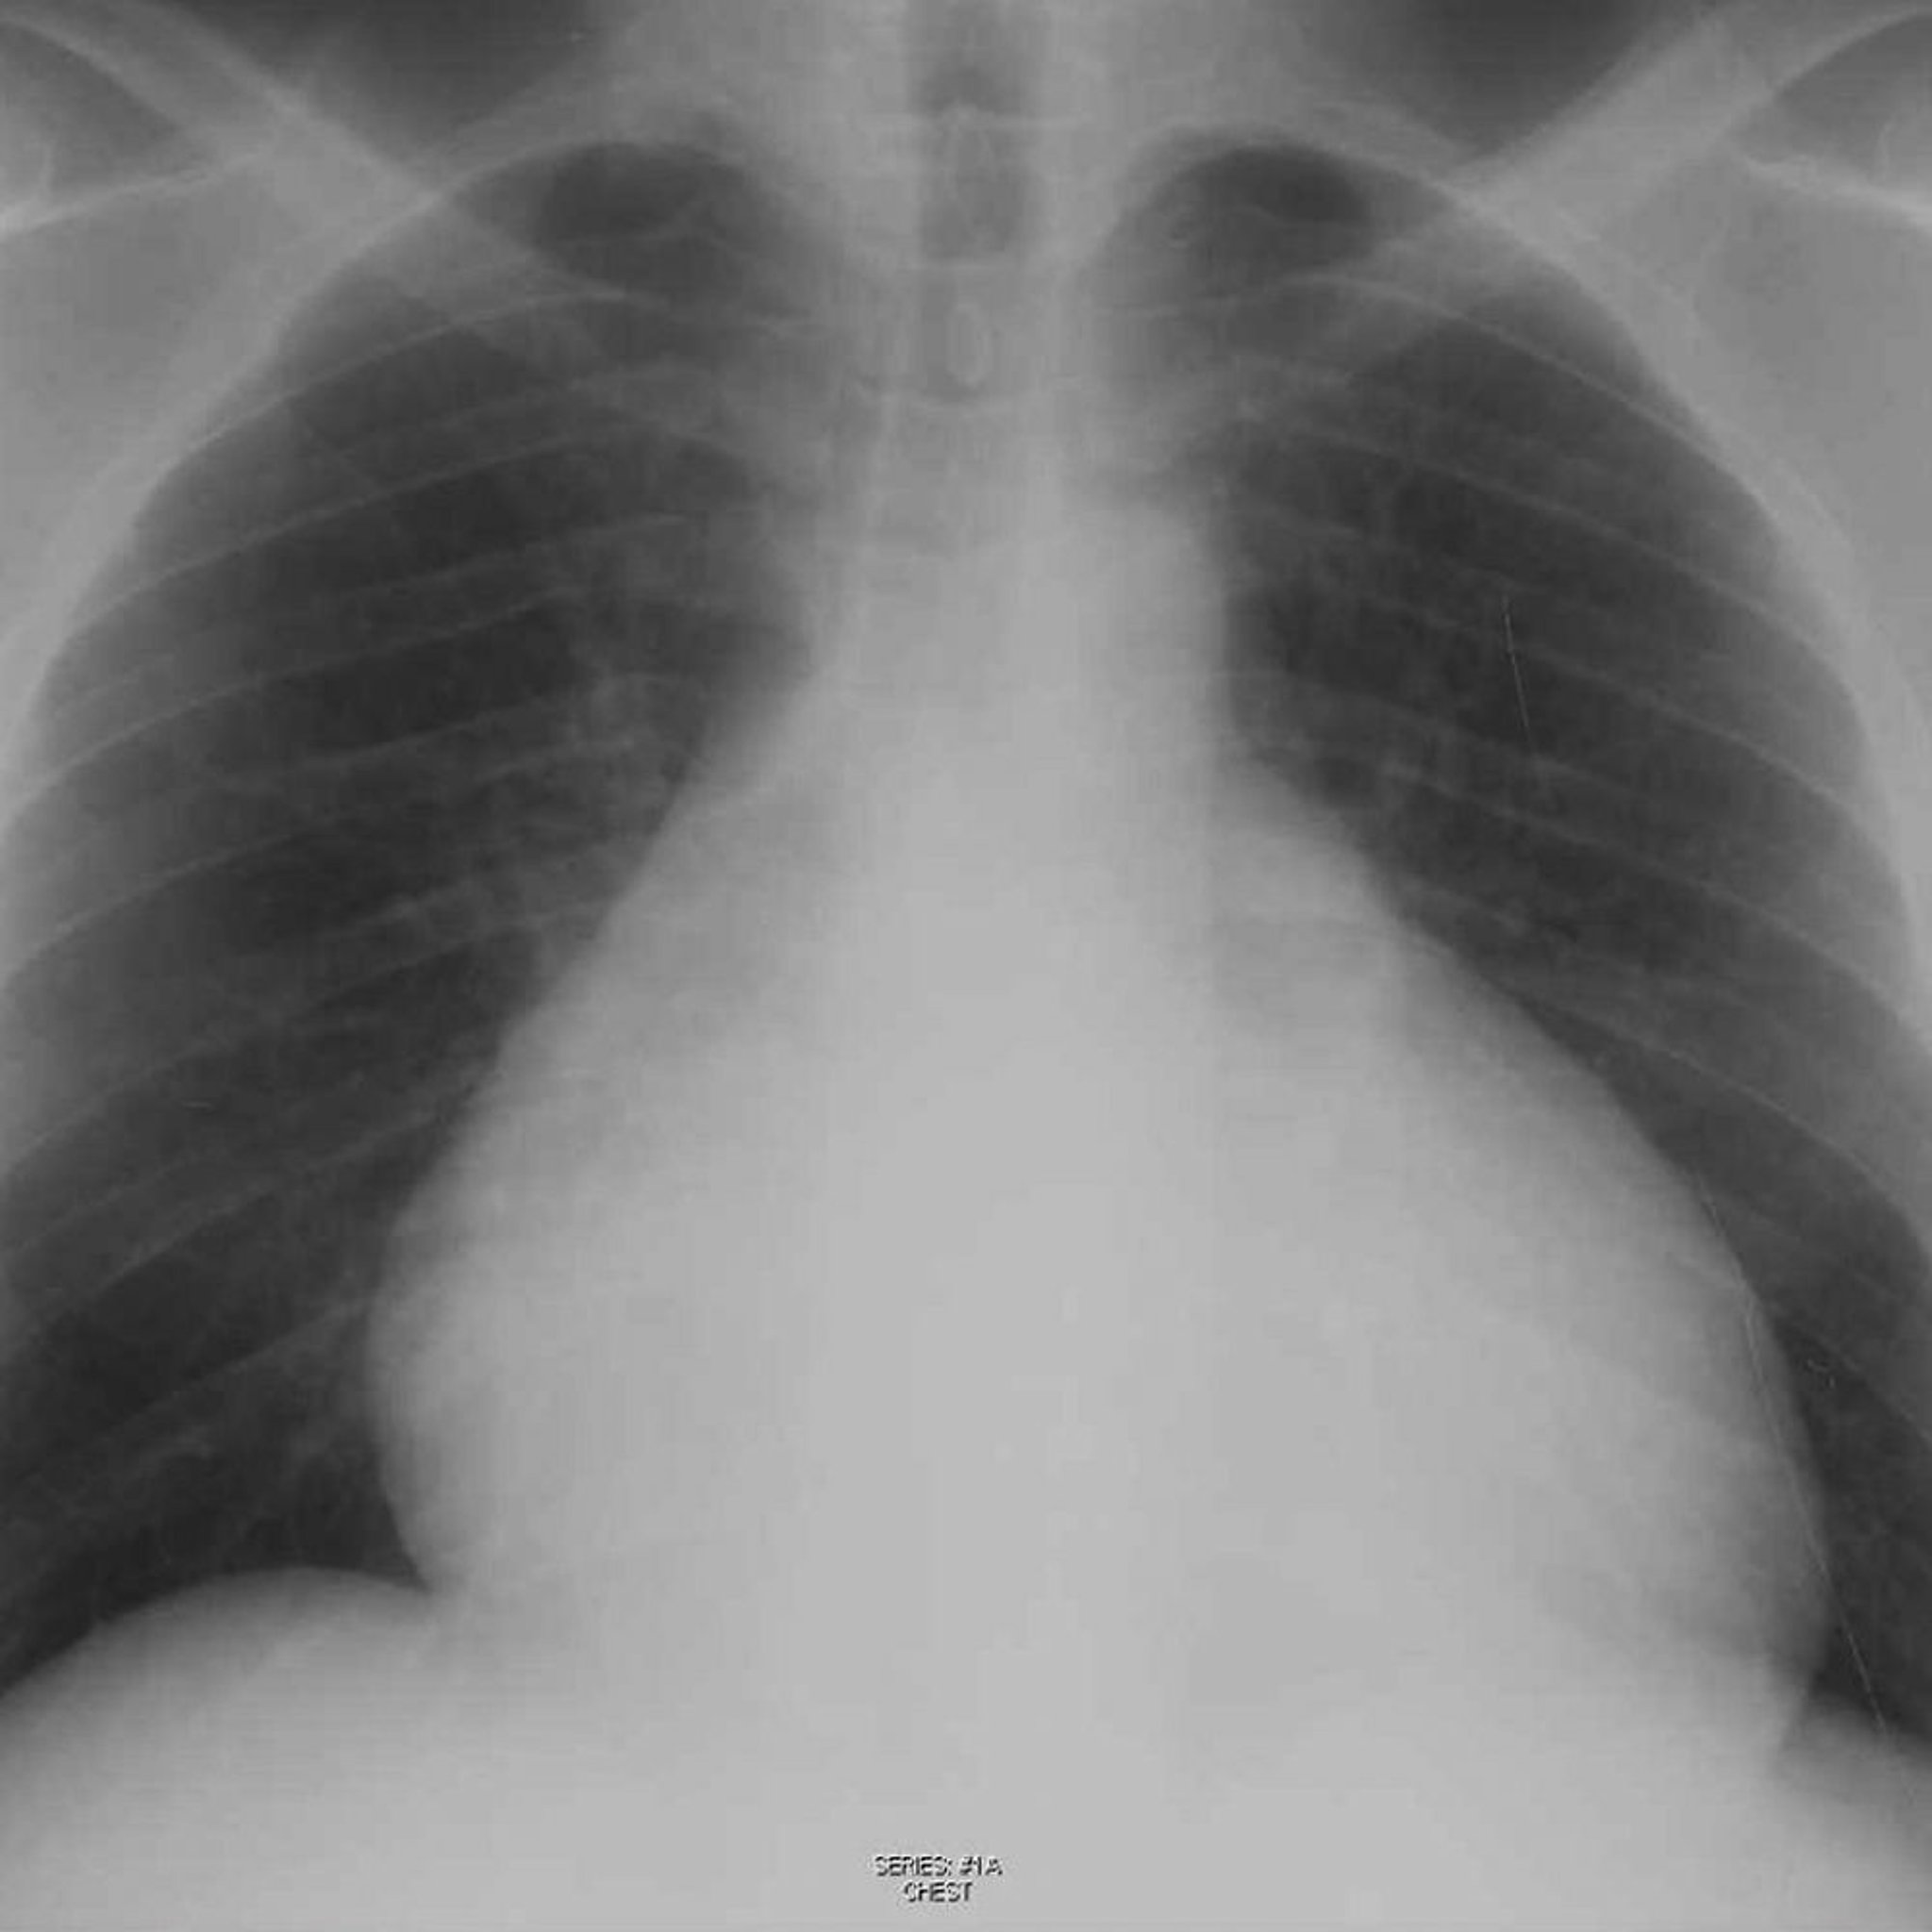

Radiolografie del torace di un paziente con versamento pericardico

Questa radiografia mostra una silhouette cardiaca ingrandita in un paziente con versamento pericardico.